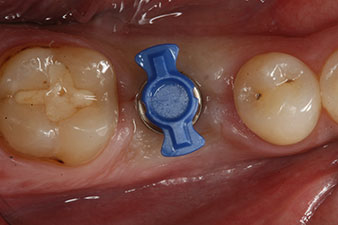

Tras la extirpación minuciosa del tejido de granulación, se incorporó el implante tal como se había planificado (blueSky, bredent).

El torque en el momento de la carga mecánica fue de 43 Ncm. Asimismo, después de atornillar un poste de medición especial adaptado al sistema de implante (SmartPeg), el valor ISQ se determinó con la sonda del módulo Osstell ISQ de W&H.

Este módulo Osstell ISQ que se encuentra disponible como accesorio para la unidad Implantmed de W&H y se acopla al motor de implantes (véase figura 11). El valor ISQ adimensional fue de 64 justo en el momento de la inserción en la dirección bucovestibular y de 68 en la dirección mesiodistal (valor máximo = 100).

Este habría permitido una cicatrización abierta o incluso un tratamiento inmediato. Sin embargo, como no se disponía de suficiente hueso en la parte crestal del implante, el área se aumentó con las virutas óseas recopiladas durante la preparación del lecho del implante y se suturó para que no penetrara saliva.